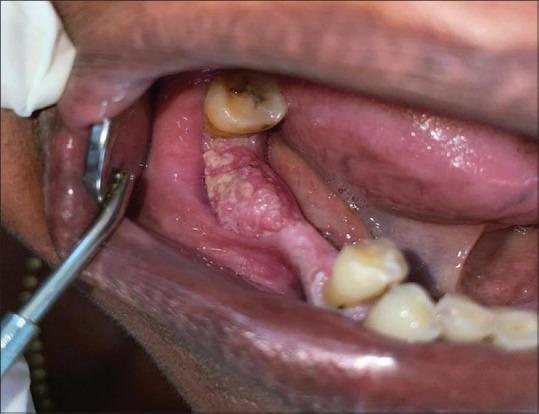

This study was conducted in the Department of Oral Medicine and Radiology from January 2019 to December 2021. All the patients were examined after recording their demographic data using a mouth mirror and probe. The diagnosis of OC was arrived based on the clinical features of the lesions. The type and duration of habits and site were recorded in clinical pro forma. The Statistical Package for the Social Sciences (SPSS) software version 21.0 was used for the statistical analysis, the Chi-square test was applied, and the significance level was set at < 0.05.

The prevalence of OC was 0.22% in our study. Of 317 cases, the majority of the patients were males ( = 204), and females ( = 113) accounted for a male: female ratio of 2:1. The most common age affected was 51-70 years with a history of tobacco chewing, followed by patients with multiple habits (smokers, tobacco chewers, and alcoholic). The buccal mucosa was the most common site followed by malignancies of multiple sites.